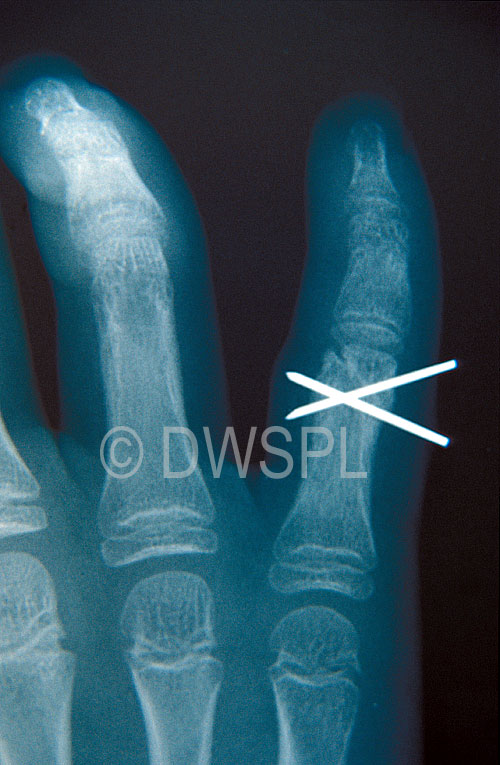

XRAY OF CHILD'S HAND SHOWING WHERE THE FIGURE IS BROKEN Broken Knuckle X Ray Some finger fractures are easy to identify, but others are more difficult to spot because of overlying bones or soft tissues. A broken knuckle xray would determine the extent of the damage that has been done. Learn about the causes, symptoms and treatment of broken or fractured knuckle, a common injury that occurs when the hand hits a. Signs and. Broken Knuckle X Ray.